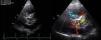

Thoracic computed tomography angiography (Figures 2 and 3) showed the Dacron tube from 2.1 cm above the aortic valve leaflets to 1.8 cm after the emergence of the brachiocephalic trunk surrounded by an image suggestive of an ascending aortic aneurysm (10 cm × 10 cm) with two active contrast leaks at the ends of the graft (type 1 endoleak), compressing the right ventricle, pulmonary artery trunk and right coronary artery.